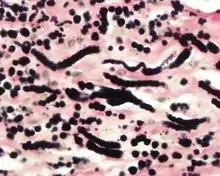

By microscopie view, there is an admixture of heavy dense bands of collagenous tissue dissected by fat and abnormal elastic fibers. The elastic fibers are often quite large and are easily identified. The elastic fibers are coarse, thick, and darkly eosinophilic, often fragmented into globules, creating a "string of pearls" or "pipe cleaner" appearance. Because of degeneration, the elastic fibers will appear as globules with a serrated or "prickled" edge.[3]

Histochemistry

The elastic fibers will be highlighted by a Weigert or von Gieson elastic stains.[7]